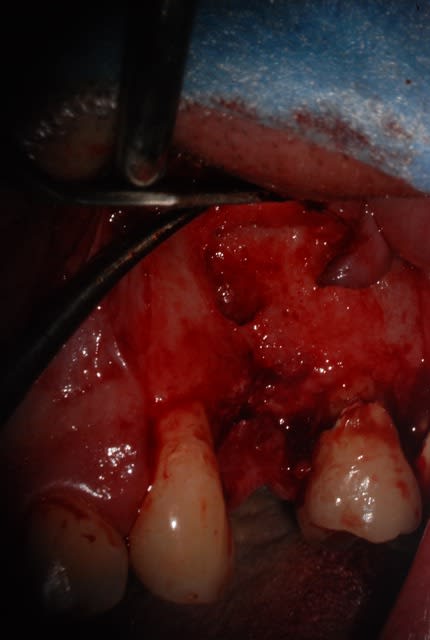

La corticale vestibulaire est présente sauf en regard de la lésion

Est ce que c'est raisonnable de faire une implantaion immédiate le jour de l'extraction avec un bon curetage de la lésion ?

Tu peux envisager l'extraction implantation en curetant bien mais fais bien attention tu as apparamment aussi une lésion sur la dent adjacente.

Tu pourrais avoir un échec à cause de cette lésion que tu n'aura pas traitée et non pas à cause de ton extraction implantation.

Prudence ...